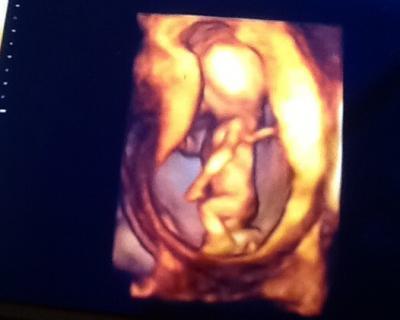

Hier mal ein Bild

Wahnsinnsbild bin schon gespannt was wir bekommen werden...

Cooles Bild. Ein 3D-Bild aus der SSW habe ich noch nie gesehen, das sieht ja mal tatsächlich wie ein Baby aus. Ich kenne nur diese verdellten und total verzogenen 3D-Bilder vom Gesicht aus der ca. 30.SSW. Aber etwas scheu ist Dein Kleines ja, so gekonnt, wie es den Kopf wegdreht.